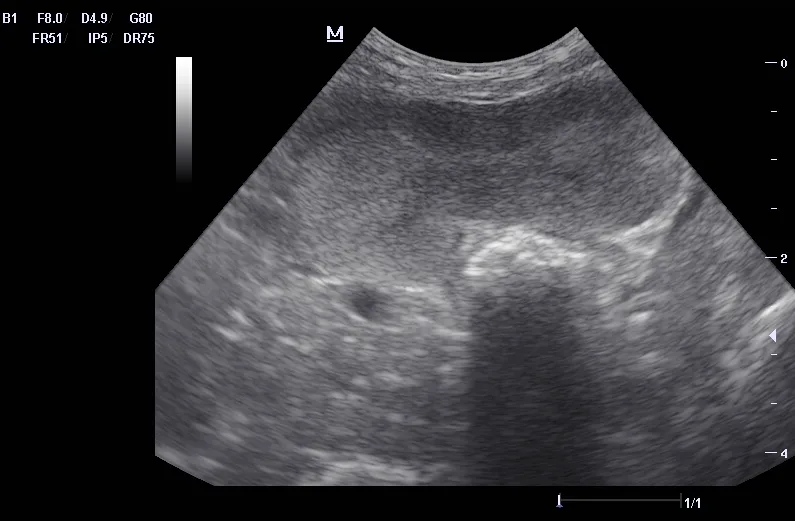

Ultrasound can be useful in evaluating the size, contour, and internal architecture of the prostate. A normal prostate appears homogeneous (Figure 1). The prostate becomes heteroechoic as a result of inflammation, hyperplasia, and neoplasia (Figure 2). The prostatic parenchyma can be focally or diffusely hypoechoic in cases of acute prostatitis or prostatic abscessation (Figure 3), as well as hyperechoic in cases of chronic prostatitis (Figure 4).

Ultrasound image of a canine prostate exhibiting chronic changes.

FIGURE 4

Prostate with chronic prostatitis. Several hyperechoic areas of mineralization can be seen.